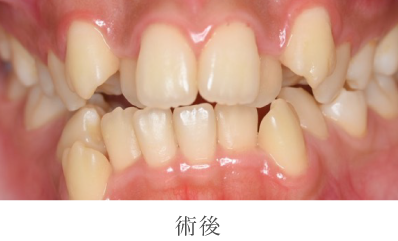

02

クリーニング・

歯科検診の詳細

- 主訴

- 口臭が気になる

- 治療期間

- 1日

- 治療内容

- 染め出し、歯石除去、ポリッシング(艶出し)

- 治療のリスク

- 術後しみる可能性があります

- 治療費

- 保険診療に準ずる

院長のコメント

全体的に歯石や汚れ(プラーク)が付着し歯肉に炎症が見受けられました。歯周病や口臭の原因である汚れを除去し磨き上げました。歯並びの影響もあり、どうしてもご自身で磨きにくい場所もありますがその際は専門である私たちに是非ご相談下さい。